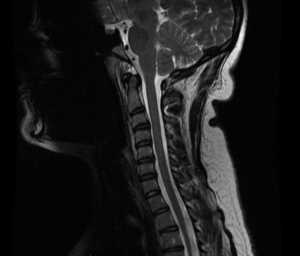

Never underestimate the potential impact of an invasive procedure on your life. Even the simplest procedures can have devastating consequences. If a complication were planned, it would not be a complication. Cervical spine surgery is delicate and carries significant risks. Even after a perfectly performed operation, swallowing issues are not uncommon. Usually, they resolve over three to four months, but some are permanent, and his turned out to be catastrophic. I don’t know if he needed the surgery or not, but it is critical to prepare yourself with a prehab program. Often, surgery is avoided.